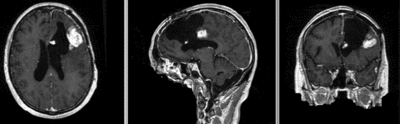

unregistered

original unregistered

rigid

affine

rigid registered affine registered

BSpline (7x7x7) unmasked

BSpline (7x7x7) masked

nonrigid registered (7x7x7 BSpline unmasked) nonrigid registered (7x7x7 BSpline masked)